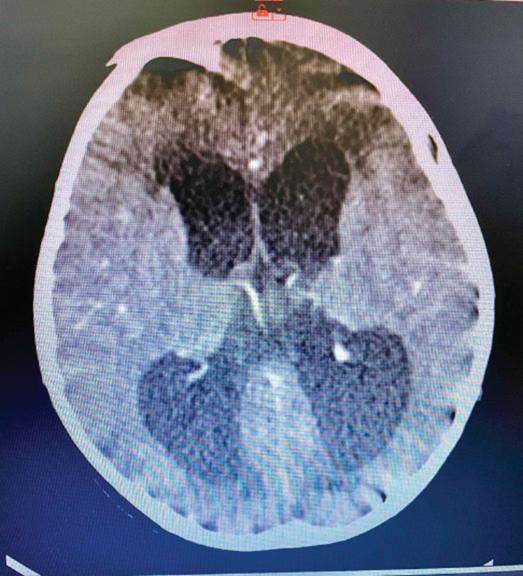

Патогенезата на заболяването, представена съвсем накратко, е следната: Mycobacterium tuberculosis→по въздушно-капков път достига до алвеоларните макрофаги, развива се бактериемия→туберкул→субарахноидално пространство→менингит. Ако от менингите бактерият достигне и до мозъчния паренхим→туберкуломи

абсцеси→ексудат от абсцесите при отварянето им инфилтрира

кортикалните и менингеални кръвоносни съдове и води до мозъчно възпаление и инфаркт. Развива се характерен базален менингит, засягат се предимно III, VI и VII ЧМН и се развива обструктивна хидроцефалия→адхезия + облитериращ васкулит + енцефалит или миелит.

Етиологичната диагноза на туберкулозния менингоенцефалит по обективни причини е възможна в 6-10% от заболелите деца. Поради това диагнозата е комплексно обусловена. Епидемиологичната анамнеза, симптоматиката на базален менингит и характеристиката на ликворния синдром са патогномонични и поставят диагнозата. Абсолютно необходимо е диагностичния процес да продължи с туберкулинов тест на Манту, микробиологично изследване на ликвор (директна микроскопия, посявка на MGIT, PCR real time, BACTEK); SPOT TB; QFT in tube; Рентгеново изследване на белите дробове; КАТ, ЯМР на мозъка.

Беше осъществено Рьо на бели дробове: липсват рентгенови данни за патологични засенчвания в белодробния паренхим двустранно. К.д. синуси – свободни. Сърце и медиастинум – б.о. Контролна КАТ на главен мозък: екстремно разширени вентрикулни отдели на ликворната система. Намален

око

цистерни. Заключение: КТ данни за тежка вътрешна хидроцефалия